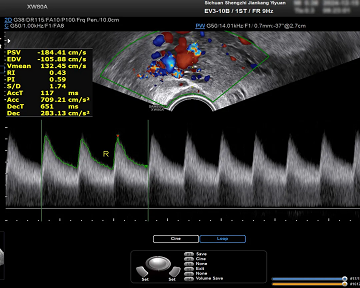

04、探寻“勃起”的动力信号

阴茎血流专项检测:能清晰观察阴茎动脉、静脉血流动力学变化,准确识别动脉供血不足、静脉泄漏等血管问题,区分动脉、静脉、混合勃起功能障碍,为性功能障碍的有针对性治疗提供准确的信号依据,帮助男性恢复健康。